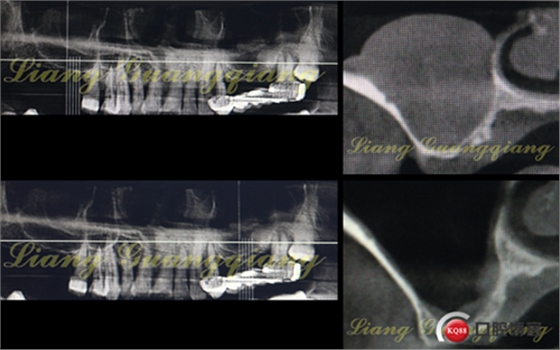

這是一周前拔牙前X光片,上頜竇內(nèi)大囊腫直徑遠(yuǎn)遠(yuǎn)>10mm。如何處理?送耳鼻喉?接下來(lái)就是預(yù)約住院,上頜竇內(nèi)手術(shù)清掃。恢復(fù)多久不知,后期是否可以繼續(xù)提升?真不好說(shuō)。

竇底骨量實(shí)在太有限,小于3mm骨高度,建議先提升植骨,二期種植。不種植就無(wú)需牙槽嵴頂切口、大翻瓣,頰側(cè)改良式切口:切口小,創(chuàng)傷小、術(shù)后反應(yīng)輕。